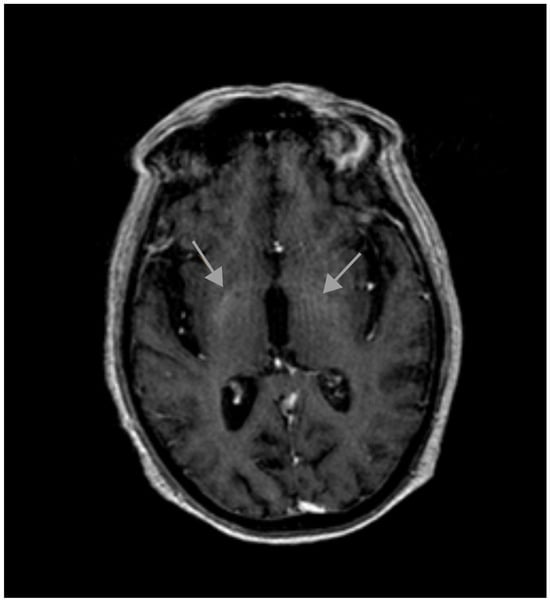

2. Case Report

2.2. Current Disease

2.3. Additional Tests